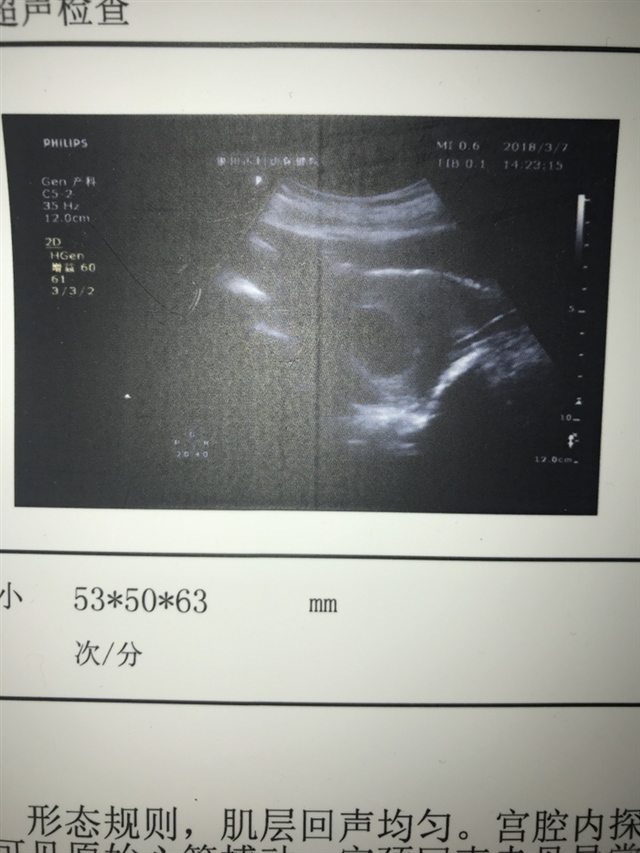

孕11周+1天

男